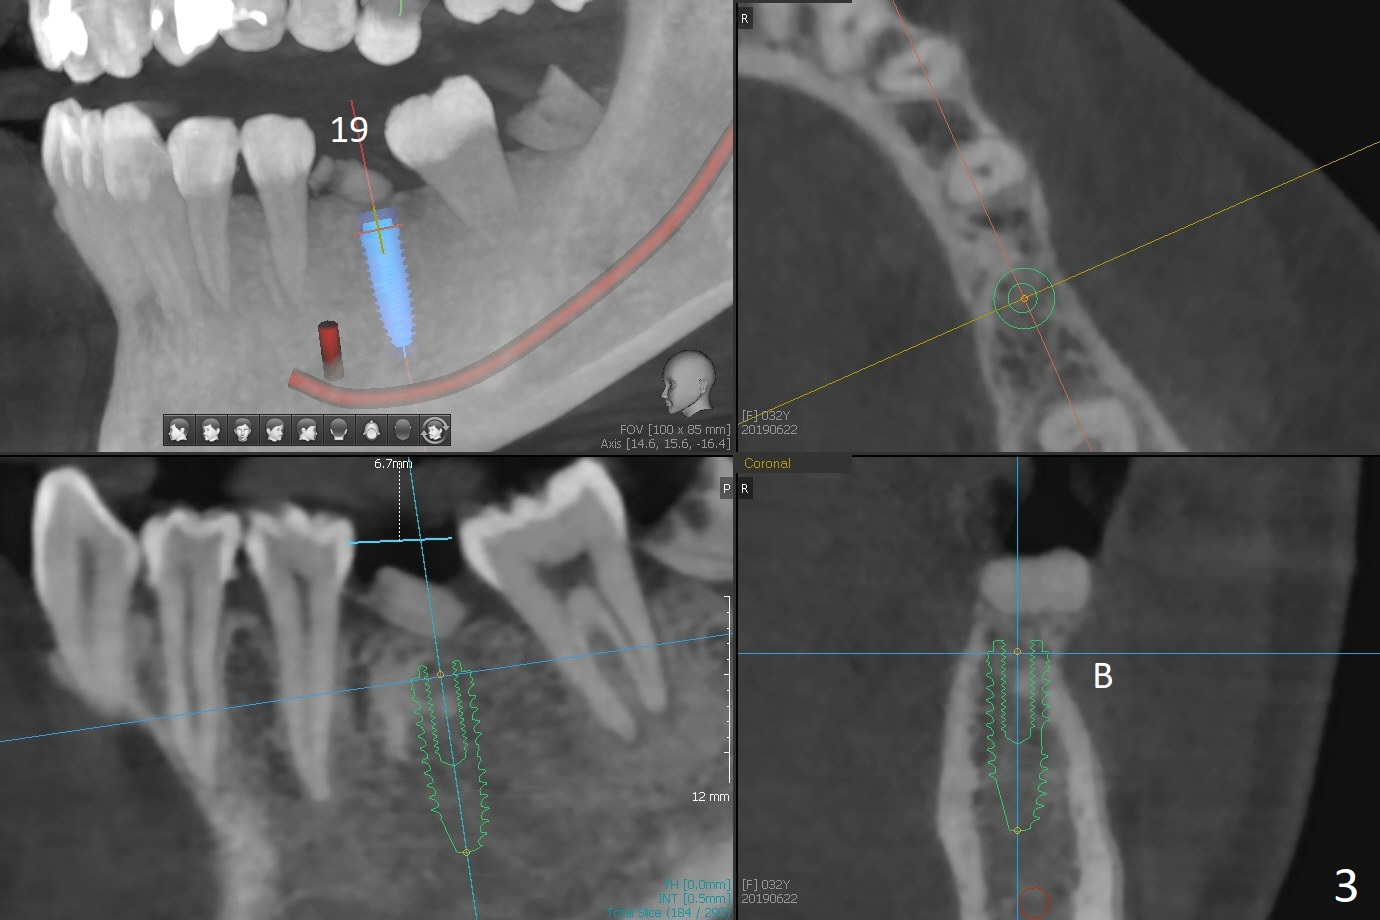

A 32-year-old woman has poor dentition: missing teeth and shifting (Fig.1). The teeth #14 and 19 will be extracted for implants (Fig.2,3 (5x8.5 and 4x11.5 mm)). Draw 2 tubes of blood for PRF. Prepare temporary and healing abutments for 14 and 19, respectively. SRP will be done with #17 extraction.